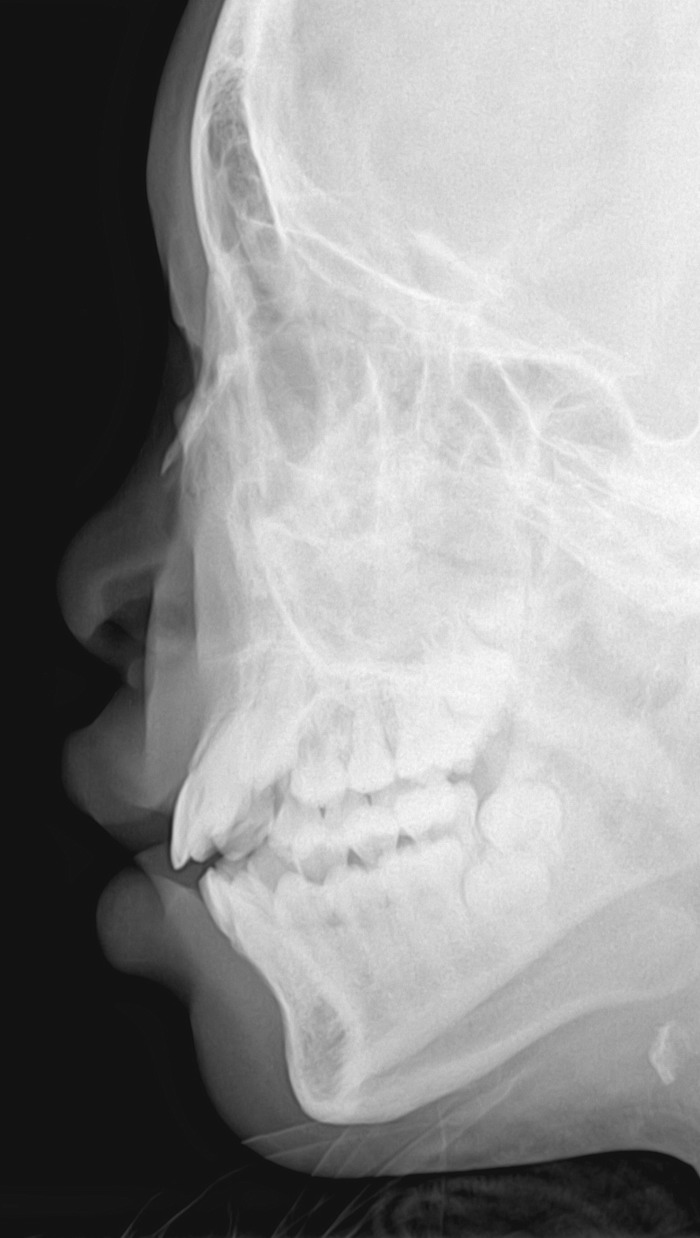

m 13y 曾打架时被人用砖砸到鼻骨左侧。该处可触到硬性肿物,请老师们给个意见...左侧近板鼻骨侧位。

未见明显骨折征像,箭头所示为软组织包块,可能是骨膜下血肿所致

可能为1、颧骨重叠可能性大。2、鼻骨骨膜血肿钙化/骨化可能性小3、上颌骨骨瘤不除外。建议加照颅骨正位片,必要时ct检查。

此鼻骨片子不是纯侧位,考虑颧骨重叠可能性大。

软组织密度影,考虑为外伤后皮下结缔增生改变,建议ct检查。

鼻骨未见明显骨折征像,考虑颧骨重叠可能,建议ct进一步检查。

肯定不是颧骨重叠影,人家已经摸的到肿块了!!!